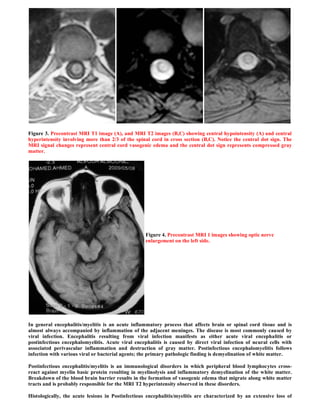

Figure 3. Precontrast MRI T1 image (A), and MRI T2 images (B,C) showing central hypointensity (A) and central

hyperintensity involving more than 2/3 of the spinal cord in cross section (B,C). Notice the central dot sign. The

MRI signal changes represent central cord vasogenic edema and the central dot sign represents compressed gray

matter.

Figure 4. Precontrast MRI 1 images showing optic nerve

enlargement on the left side.